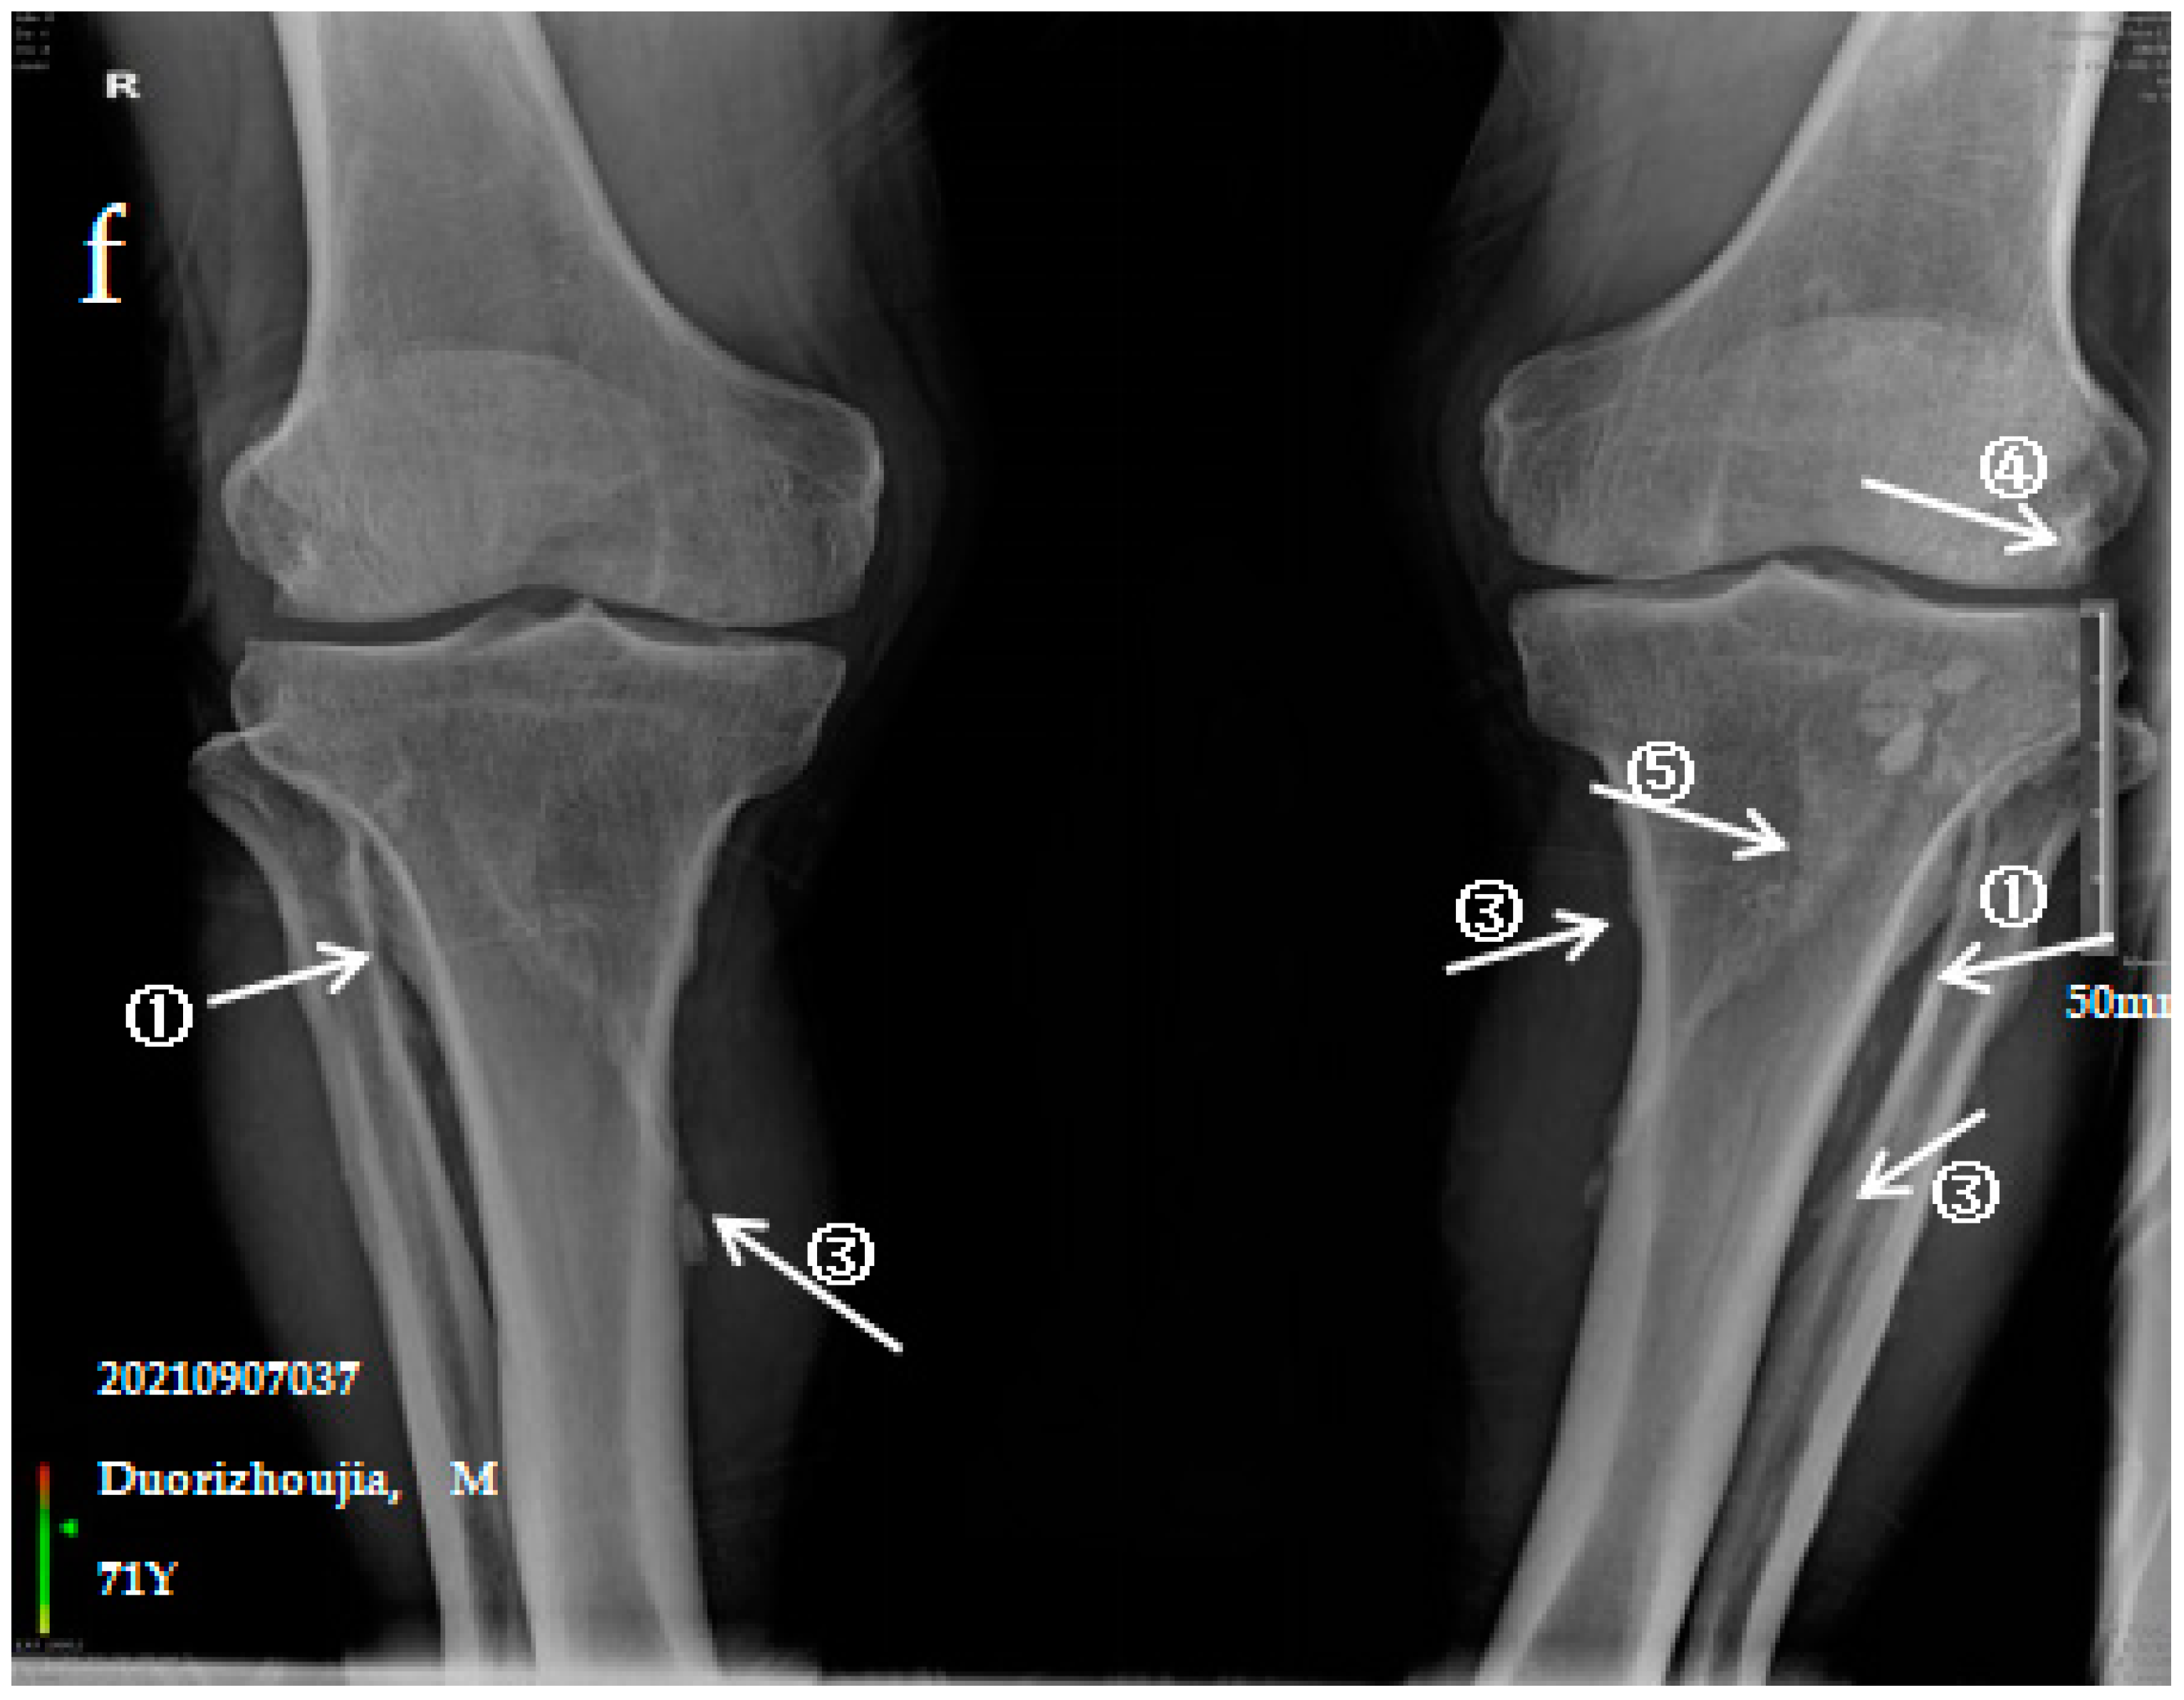

Figure 1.

X-ray imaging of SF patients. The anteroposterior actinogram of the upper limb (a) and both lower limbs (b) of patient with mild SF, the anteroposterior actinogram of the upper limb (c) and both lower limbs (d) of patient with moderate SF, the anteroposterior actinogram of the upper limb (e) and both lower limbs (f) of patient with severe SF. ①: ossification of interosseous membrane; ②: degeneration of the elbow joint; ③: Ossification shadow; ④: Ossification of knee joint capsule; ⑤: ossification of soleus tendon.

3.2.3. Case Analysis of a Patient Diagnosed by X-ray with Severe SF

The patient is a 71-year-old male with severe bone and joint pain, limited activity and no ability to work. The anteroposterior actinogram of the upper limb (Figure 1e) shows obvious ossification of the interosseous membrane of the ulna and radius, forming a large fin-like ossification near the ulna and radius. The pronator teres muscle tendon shows obvious ossification, and a stalactite ossification shadow can be seen in the radial head. There is obvious degeneration of the elbow joint. The anteroposterior actinogram of both lower limbs (Figure 1f) shows ossification of the tibiofibular interosseous membrane, with a colliculus appearance. The peroneus longus tendons show obvious ossification, as do the soleus tendon, knee joint capsule and tibial collateral ligament.

Ossification of the interosseous membrane has a high incidence and specificity in SF and is one of the important diagnostic signs of SF. Ossification of the interosseous membrane was more obvious in patients with severe SF than in those with mild or moderate SF.